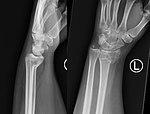

Colles' fracture Abraham Colles distal radius fracture with dorsal angulation, impaction and radial drift fall on outstretched hand Colles' fracture at Who Named It? Colles fracture1.png

Smith's fracture Robert William Smith distal radius fracture with volar displacement fall on outstretched hand with wrist in flexed position Smith's fracture at Who Named It? Smith2019Frac.jpg